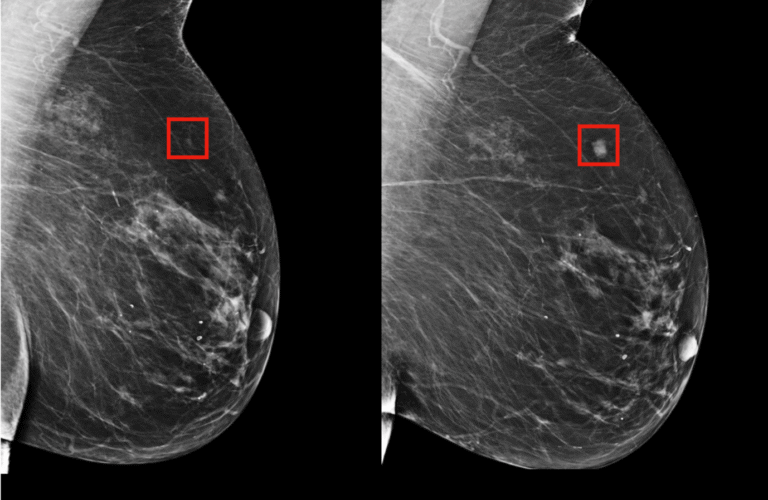

This AI Found Cancer Doctors Missed — Is It the Future of Diagnosis?

A revolutionary new wave of artificial intelligence is reshaping oncology. Recent clinical trials show that AI in…